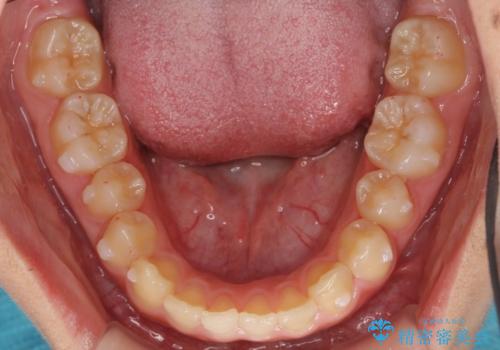

- 前歯の並びを主訴に来院。

前歯が出ており、また、左上の側切歯が1本生まれつき少ない状態でした。

また、右の奥歯の関係も上が前にある状態で大きくずれていました。

今回は左右とも1歯対2歯の関係であるため、それは変えずに前歯を可及的にひっこめて足りない部分をブリッジで補う治療としました。

奥歯の関係を完全に1級にするには右上の小臼歯の抜歯が必要でしたが、もともと左上の前歯が生まれつき少ないため今回は歯を抜かずに治療しています。